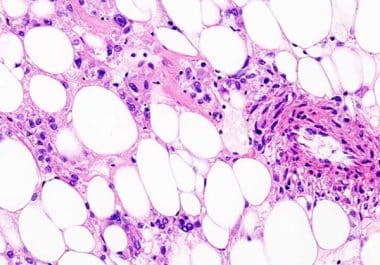

The FDA approved a kinase inhibitor for the treatment of inflammatory myofibroblastic tumors in children and adults. The U.S....